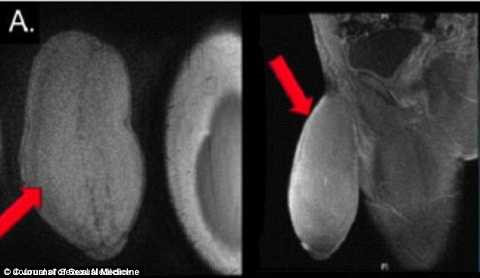

3. Tái tạo dương vật

Một thanh niên 17 tuổi người Mỹ đã trải qua cuộc phẫu thuật dương vật lần đầu tiên trên thế giới do “cậu nhỏ” quá lớn khiến cậu mất khả năng quan hệ tình dục và tham gia các trò chơi mang tính cạnh tranh.

Khi được gia đình đưa tới gặp các bác sĩ, tất cả đều ngạc nhiên với kích thước của cậu nhỏ bởi chiều dài lên tới 17 cm và chu vi 22 cm (tương đương 1 quả bưởi nhỏ).

Với kích thước khác thường như thế, cậu thường xuyên phải chịu những cơn đau, sung phồng do lưu thông máu bị gián đoạn, thậm chí cương cứng. Chính vì vậy mà cậu luôn cảm thấy tự ti với hình dạng của nó và cậu luôn khó chịu khi quần rộng cũng không che giấu được với mọi người.

Cuối cùng, các bác sĩ đã quyết định bắt tay vào cuộc phẫu thuật thường sử dụng kỹ thuật điều trị bệnh Peyronie. Các bác sĩ phải tiến hành tháo da của dương vật và cắt bỏ nhiều phần mô nhỏ xung quanh. Khi phẫu thuật xong, niệu đạo và dây thần kinh xúc cảm của bệnh nhân đều hoạt động bình thường. Và đó là ca phẫu thuật lạ lùng đầu tiên trên thế giới.